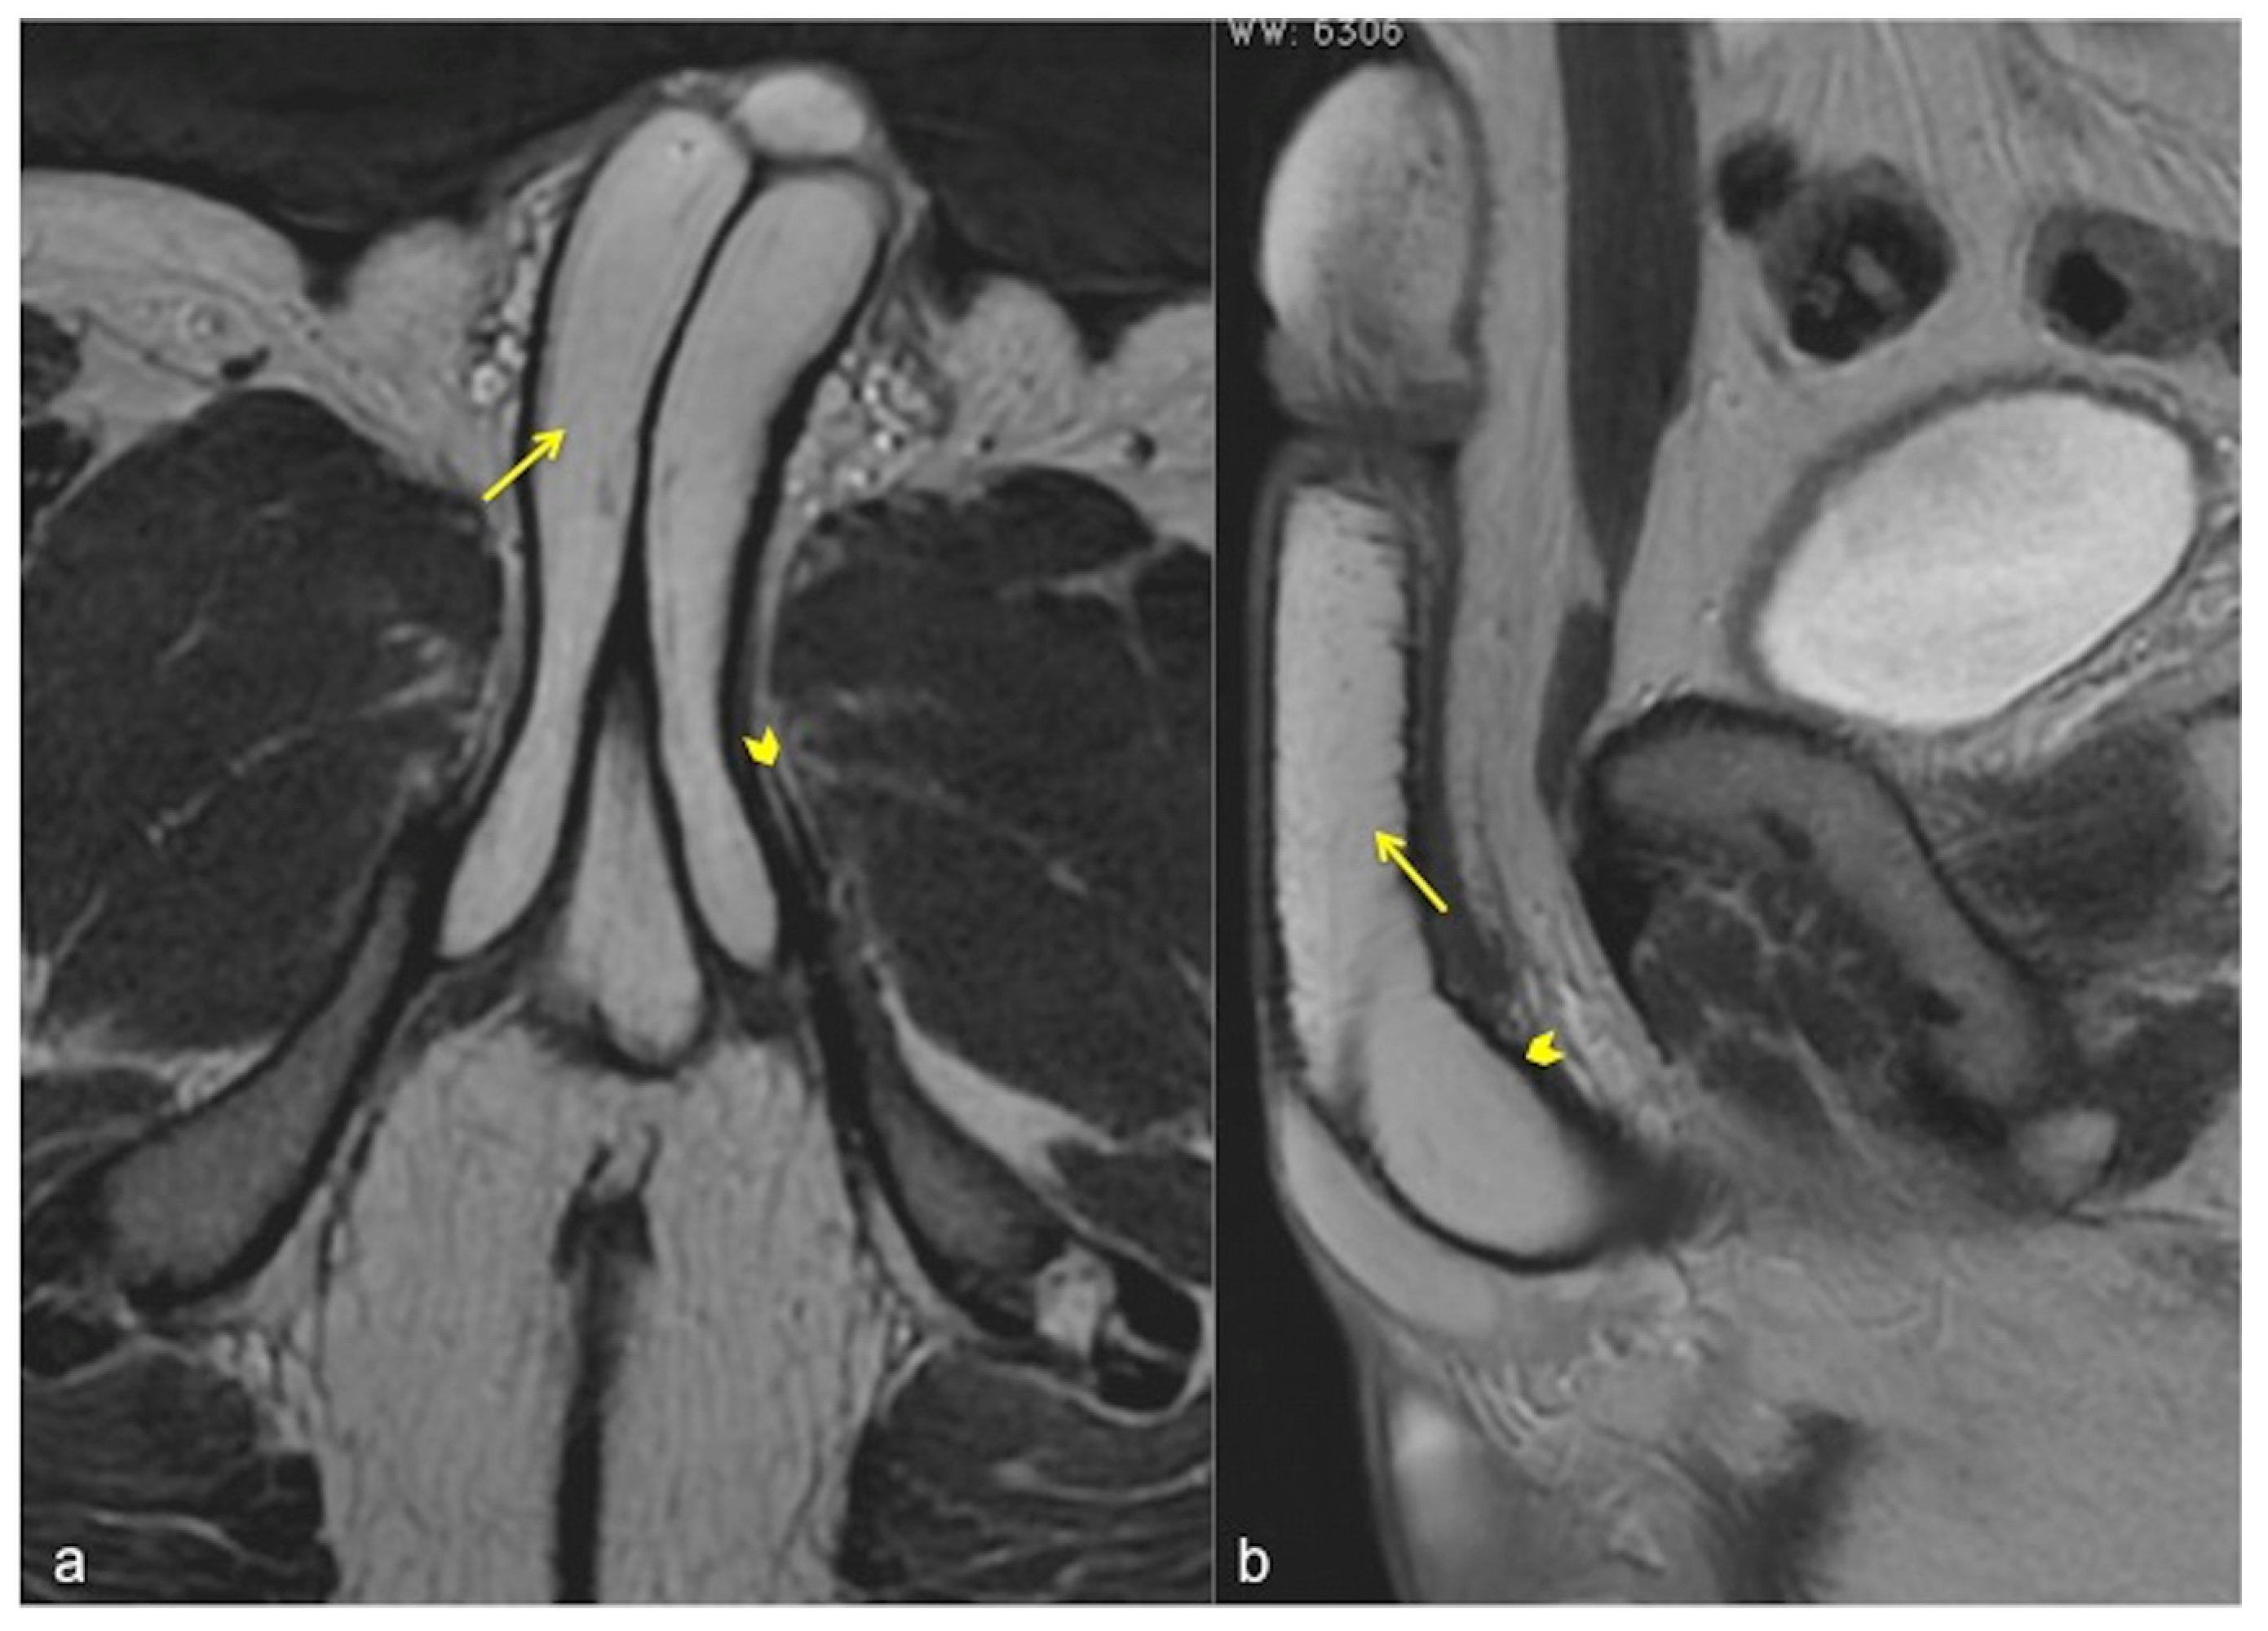

Figure 5.

Normal anatomy of the penis. Axial (a) and sagittal (b) SSFSE T2W MRI images showing high signal intensity of the cavernous bodies and of the corpus spongiosum ((a,b), straight arrows), while the adjacent tunica albuginea has low signal intensity (arrowheads).